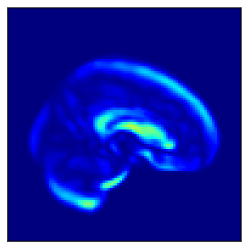

Fig. 5 shows the difference in the reconstructed images (the coronal, sagittal, transverse planes) with and without perturbation to one dimension of the low-dimensional representations that most affect the disease features between AD and CN. This one dimension is chosen to have the largest expected value of the difference in the mean vector ( dim) between AD and CN.

In Fig. 5, the influence of dimensions that may contribute to the diagnosis of AD is examined, and it can be seen that the naïve -VAE captures not only the important areas around the ventricles shown in Fig. 2 but also the edges of the brain and other areas. Loc-VAE, however, is more limited and captures this region better. This result shows that Loc-VAE acquires a specific dimension of the disease features on low-dimensional representation. Disease feature–specific dimensions serve as materials for the neurologist to assess similar cases displayed by CBIR.